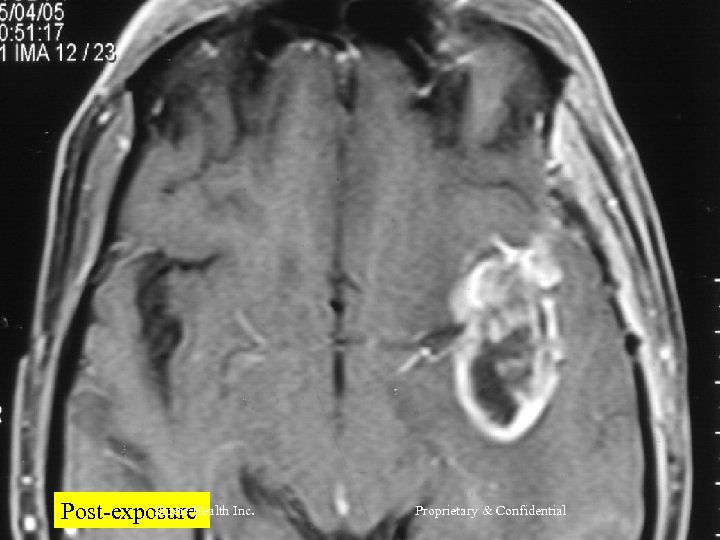

CASE 2 Mr R, 56 yrs l Nov 2004 – MRI Brain = Left frontal SOL (4 x 3 cm) - SX = Craniotomy x decompression of insular glioma HPR = Glioblastoma Grade IV l RT – 60 Gy/30 # till Jan 2005 l CT – Temedol x 2 # till Feb 2005 l Shreis Health Inc. Proprietary & Confidential

l l Presented Feb 05 - Loss of memory - Apathetic - Hemiparesis ® (power 3/5) Today after 1 course of RFQMR - No focal/Gen Neuro deficit - Normal higher functions and back to work. Shreis Health Inc. Proprietary & Confidential

Shreis Health Inc. Post-exposure Proprietary & Confidential

Shreis Health Post-exposure Inc. Proprietary & Confidential